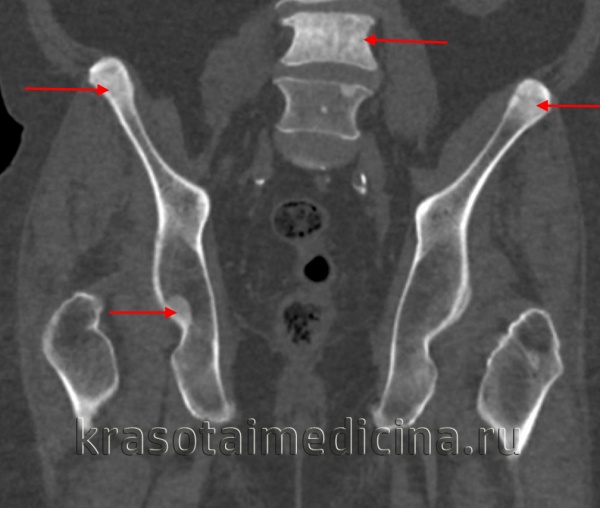

Компьютерная томография

При МСКТ видны участки резко уплотненной структуры, расположенные так, что создается впечатление о якобы происшедшем «стекании» остеосклеротических масс кости с вышерасположенных на нижерасположенные отделы. Поражаются преимущественно длинные и короткие, а также мелкие кости конечности , реже лопатки и тазовые кости.

Уплотнение структуры наблюдается не на всем протяжении пораженной кости, а на определенном ее участке, преимущественно эксцентрично.

Помимо склерозирования губчатого вещества кости, при М. нередко наблюдается гиперостоз пораженных костей.

Диагностика в основном основана на обычной рентгенографии. На рентгенограммах мелореостоз представлен как линейные поражения повышенной плотности кости вдоль большой оси (стволы или диафизы) трубчатых костей. Повреждения приводят к увеличению толщины коры и могут распространяться на внешнюю поверхность костей, создавая видимость «стекающего со свечи воска». При полиостатическом поражении линейные поражения, как правило, непрерывны вдоль одной и той же стороны пораженной конечности и «прыгают» через суставы. Может наблюдаться кальцификация мягких тканей и даже внематочная окостенение.

![КТ таза. Множественные склеротические очаги в костях таза и позвонках вторичного опухолевого характера.]()

КТ таза. Множественные склеротические очаги в костях таза и позвонках вторичного опухолевого характера.